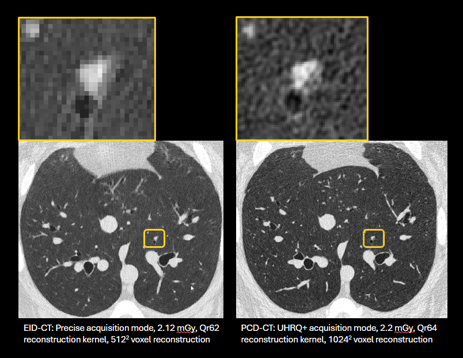

Our group has worked on the optimization of CT imaging protocols and/or validation of quantitative CT biomarkers for the assessment of lung structure. The focus to date has been on assessment of low and ultra-low dose radiation levels on quantitative lung structure assessment. Ongoing work is focused on new photon counting detector CT (PCD-CT) scanner technology.

Sieren JC, Schroeder KE, Kitzmann J, Knoernschild K, Atha J, AlArab N, Guo J, Fain SB, Hoffman EA. Ultra-High Resolution Photon Counting Detector Computed Tomography Imaging for Quantitative Lung Assessment -An Anthropomorphic Phantom Study. Investigative Radiology 2025 (In Press)